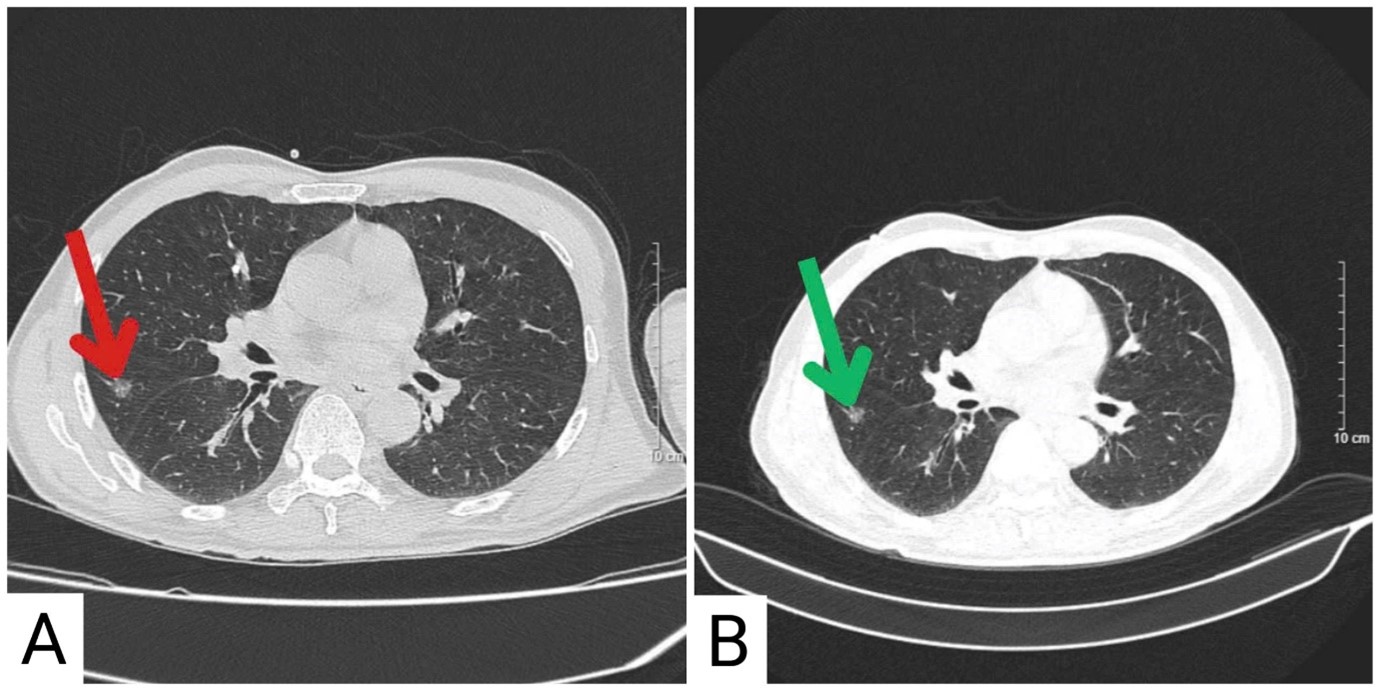

So sánh hình ảnh cắt lớp vi tính lồng ngực trước điều trị và sau 4 tháng điều trị

Hình 5. Hình ảnh chụp cắt lớp vi tính lồng ngực trước và sau điều trị

A. Hình ảnh chụp cắt lớp vi tính lồng ngực trước điều trị: Nốt bán đặc thuỳ giữa phổi phải đường kính 8,5mm (mũi tên đỏ)

B. Hình ảnh chụp cắt lớp vi tính lồng ngực sau điều trị: Nốt đặc thuỳ dưới phổi trái (mũi tên xanh lá cây) kích thước 9mm (không tăng so với trước điều trị), không xuất hiện thêm tổn thương thứ phát.